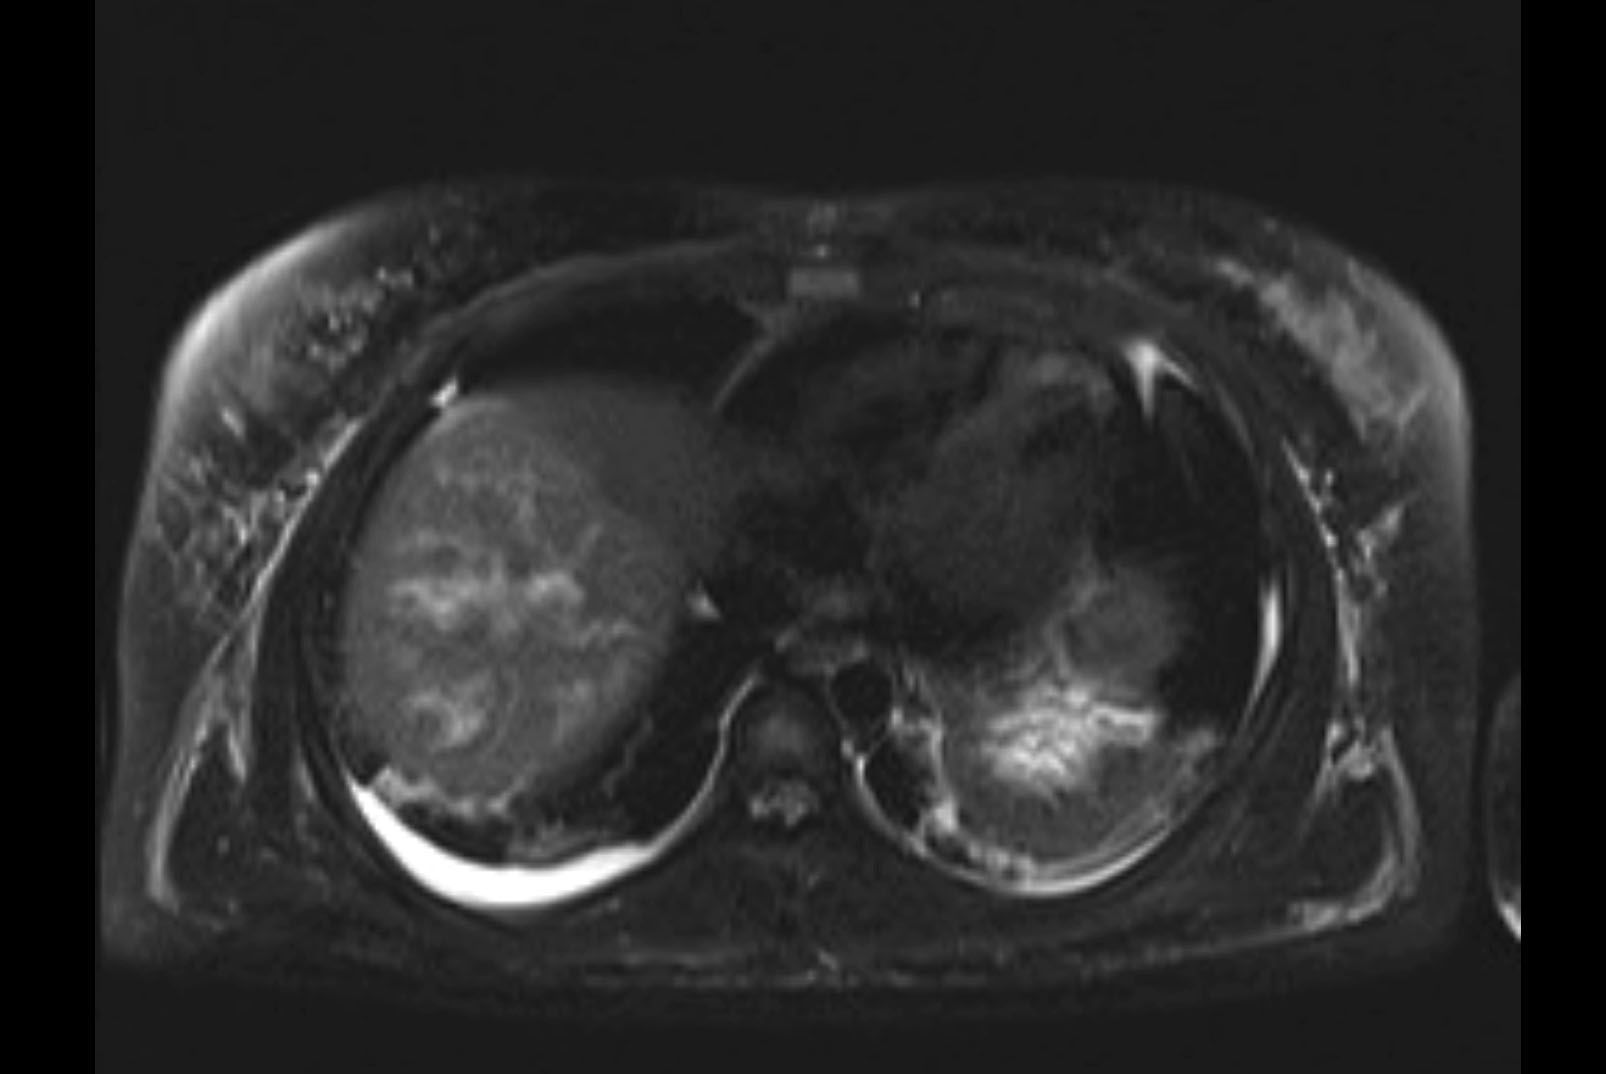

MRI T2